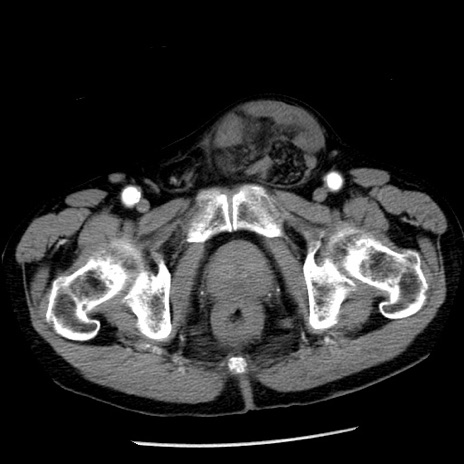

症例26(横断像)

【症例】80歳代男性

【主訴】嘔吐

【現病歴】昨晩2回嘔吐あり、今朝になっても嘔吐あり。来院。

【既往歴】胃潰瘍

【身体所見】意識清明、BT 37.6℃、BP 166/95mmHg、HR 100bpm、SpO2 97%、腹部:平坦・軟、腸蠕動音聴取良好、圧痛なし。

【データ】WBC 21900、CRP 1.46